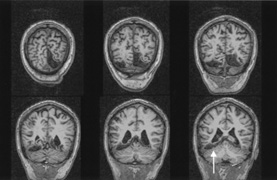

Fig. 10. Striate quadrantanopia. A. A 68-year-old woman with a stroke 3 years previously, causing left inferior quadrantanopia. B. MRI shows infarct of the superior bank of the right calcarine cortex.